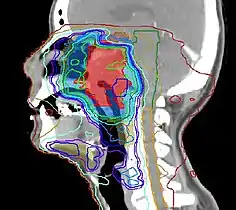

Nuclear Medicine is a fascinating application of nuclear physics. The first ten chapters of this wikibook are intended to support a basic introductory course in an early semester of an undergraduate program. Additional chapters cover more advanced topics in this field.

Radiation Oncology is a concise review of the radiation oncology field including a review of pertinent literature. Designed as a primer for students of radiation oncology, but may also be useful for those in practice to review areas of interest.